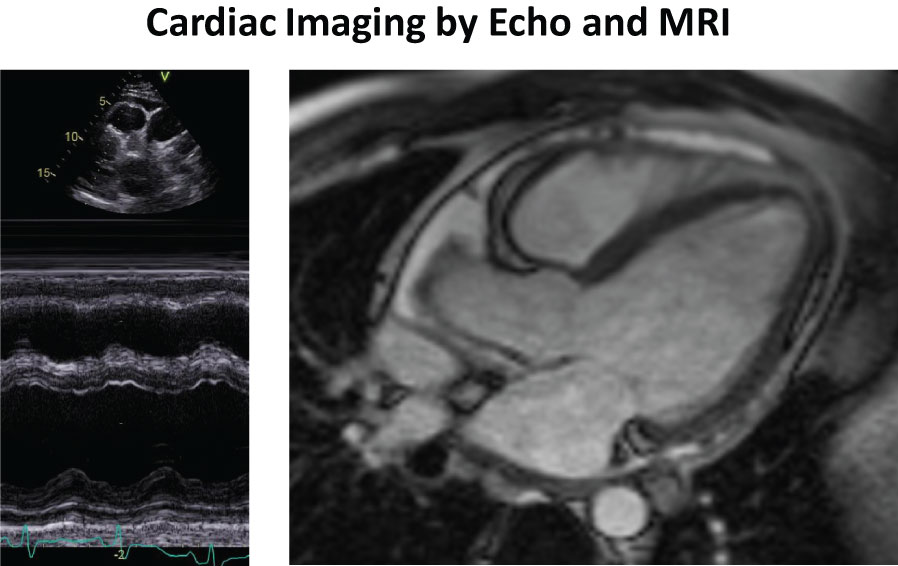

Upon echocardiography, a pericardial effusion and slightly decreased left ventricular pump function (EF 49%) were noted (Figure 1a). Upon cardiac MRI, slightly decreased left ventricular pump function was confirmed (EF 48%) and fibrosis was excluded by absence of late gadolinium enhancement (Figure 1b). Upon coronary angiography, there was no evidence of coronary arteriitis or obstructive coronary artery disease. On ventriculography, elevated filling pressures and slightly reduced left ventricular function were noted. Laboratory testing revealed an increased titer of antinuclear antibody (ANA, 1:1000) but no antibodies against ds-DNA, p-ANCA or c-ANCA. Further tests for rheumatoid arthritis (rheumatoid factor (RF), Anti-cyclic citrullinated peptide (Anti-CCP)), sarcoidosis (soluble interleukin 2 receptor (sIL-2R), angiotensin-converting enzyme (ACE)), borreliosis (serology test), tuberculosis (QuantiFERON, sputum) and other infectious diseases were negative. On the basis of these findings, a diagnosis of acute exacerbation of undifferentiated connective tissue disease with associated (peri-)carditis was established.

Figure 1: a, left) M-mode Echocardiography showing pericardial effusion and slightly decreased LV-function; b, right) Cardiac MRI showing presence of pericarial effusion and absence of late gadolinium enhancement. View Figure 1